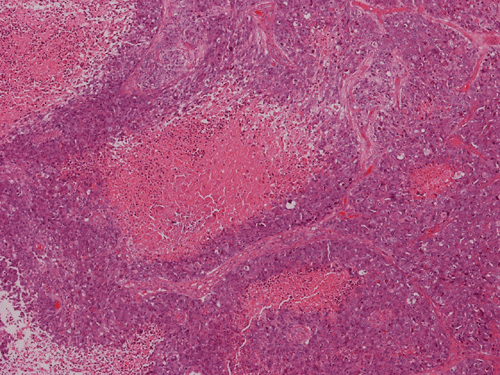

The volume of tissue received for examination amount to an aggregate of 4.0 x 2.0 x 1.5 cm in combined size. Grossly, the tissue is soft and has a creamy color with hemorrhage. The intraoperative cytologic preparation demonstrate a neoplasm composed with small to medium sized blue cells that smear out rather homgeneously and evenly. If you pay attention, there are some larger cells with a substantial amount of cytoplasm even at low magnification (Panel A). On high magnification, the nuclei are rather uniformly large, with high grade of pleomorphism, and almost all cells contain a distinct nucleoli. Apoptotic bodies and mitoses are frequent (Panel B). There are also large cells with prominent nucleoli and substantial amount of eosinophilic cytoplasm. These cells are suggestive of rhabdoid cells but none of them have the distinct inclusion body like cytoplasmic eosinophilic body of the rhabodid cells in atypical teratoid rhabodid tumor (Panel C). In the frozen section, both small to medium sized cells and cells with large nuclei with large, prominent, and eosinophilic nucleoli (Panel D and E). In the permanent sections, there is extensive necrosis (Panel F). The histology is in general agreement with that of frozen section except that the tumor cells appear to have more cytoplasm and more plemorphic, large nuclei with prominent nucleoli in comparison to the frozen section (Panel G). Large cells with substantial volume of cytoplasm, large, bizarre nucleoli and prominent, eosinophilic nucleoli are also noted (Panel H). There is a generalized degree of high grade pleomorphism. Results of immunohistochemistry are as follow:

Large cell and anaplastic medulloblastomas are recognized as different variants in the new WHO classficiation 1. They share many basic features with medulloblastoma 2, 3. The most notable differences are large cell size, increased variation of nuclear size, prominent and even eosinophilic nucleoli, increased mitotic figures and number of pyknotic or apoptotic cells, and extensive, geographic areas of necrosis. In the experience of the authors, most of the tumor cells in large cell and anaplastic medulloblastomas have high nuclear to cytoplasmic ratio in a manner similar to that of the classic variant. As per the new WHO classification, large cell medulloblastomas are composed mainly of large cells with more cytoplasm than the classic variant or the anaplastic variant. In the experience of the authors, this distinction is not always possible. The case being illustrated here includes some large cells with substantial amount of cytoplasm and but these cells only represent a portion of the tumor cell population. In general, anaplastic and large cell medulloblastomas have less favorable prognosis than the classic variant of medulloblastoma. However anaplastic changes are uncommon and does not affect the prognosis in adult cases as per one study 4.